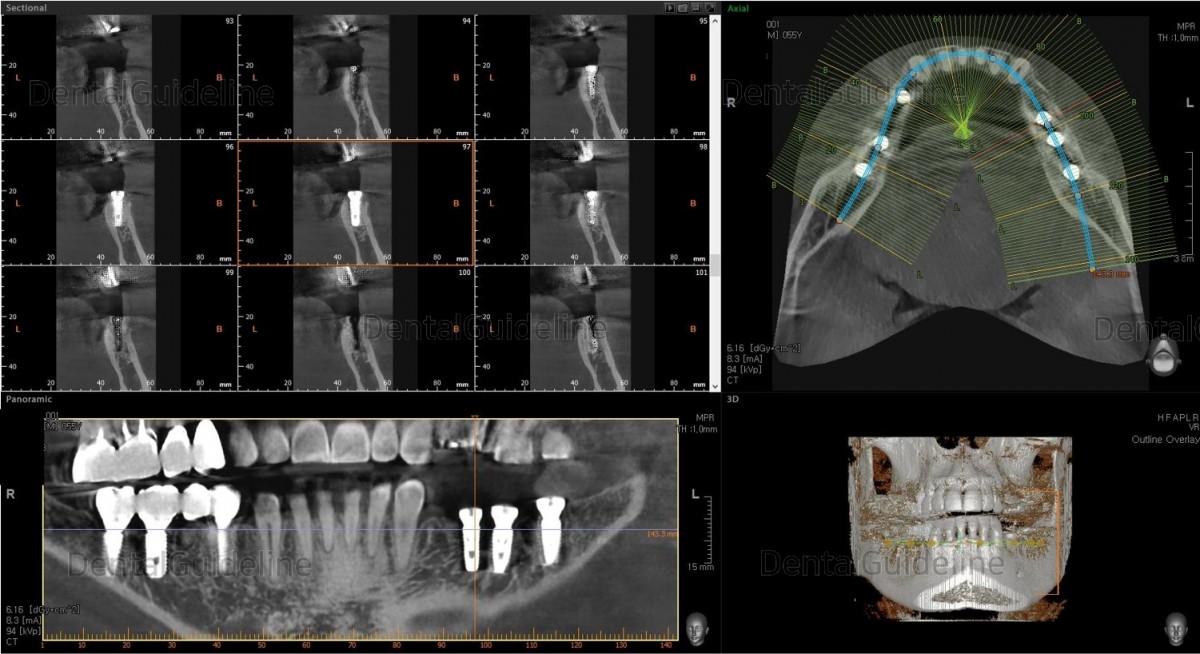

Surgery simulation to find the optimal

size, position, and direction of implants.

2nd premolar –Arum NB

Ø4.0L10 (30Ncm), 1st molar-Arum NB

Ø5.0L10 (40Ncm), 2nd molar-Arum NB

Ø5.0L10 (30Ncm),